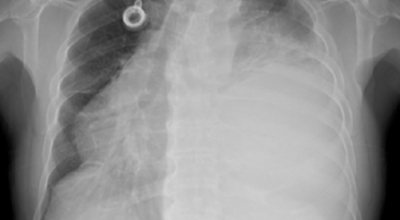

폐암 검사는 X-ray를 통해서 검사하는데 , 크기가 작거나 구석에 위치한 경우 확인이 어려운 경우도 있답니다. 그리고 조직 검사를 통해서 정확한 진단을 하게 되어요. 폐암이 발견되면 종양의 크기나 전이 여부 , 위치에 따라서 수술 여부를 결정하게 됩니다.